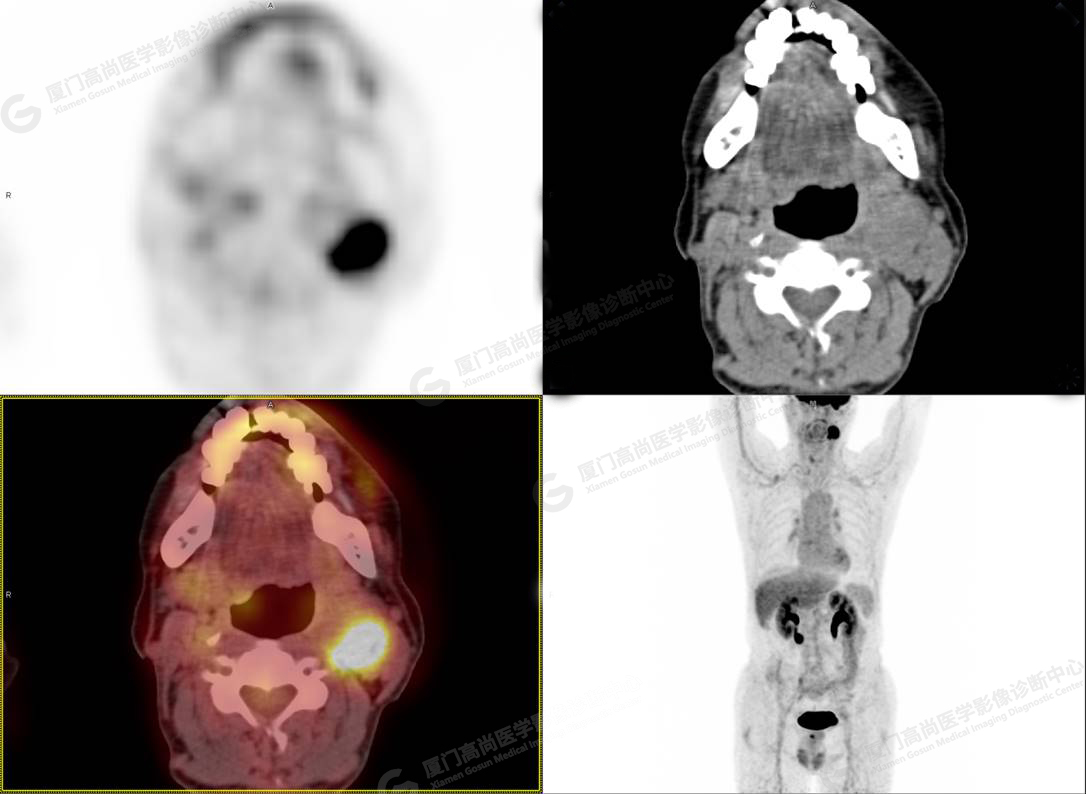

PET/CT影像圖

圖2

PET/CT所見:左側頸部(II區(qū))見腫大淋巴結,大小約2.5cm×2.3cm,其內密度不均,邊界尚清,放射性攝取異常增高,早期SUVmax 11.5,延時SUVmax 14.5。

影像診斷: 左側頸部(II區(qū))腫大淋巴結,代謝異常增高,考慮腫瘤性病變可能性大(淋巴瘤?轉移瘤?),建議病理學檢查明確。